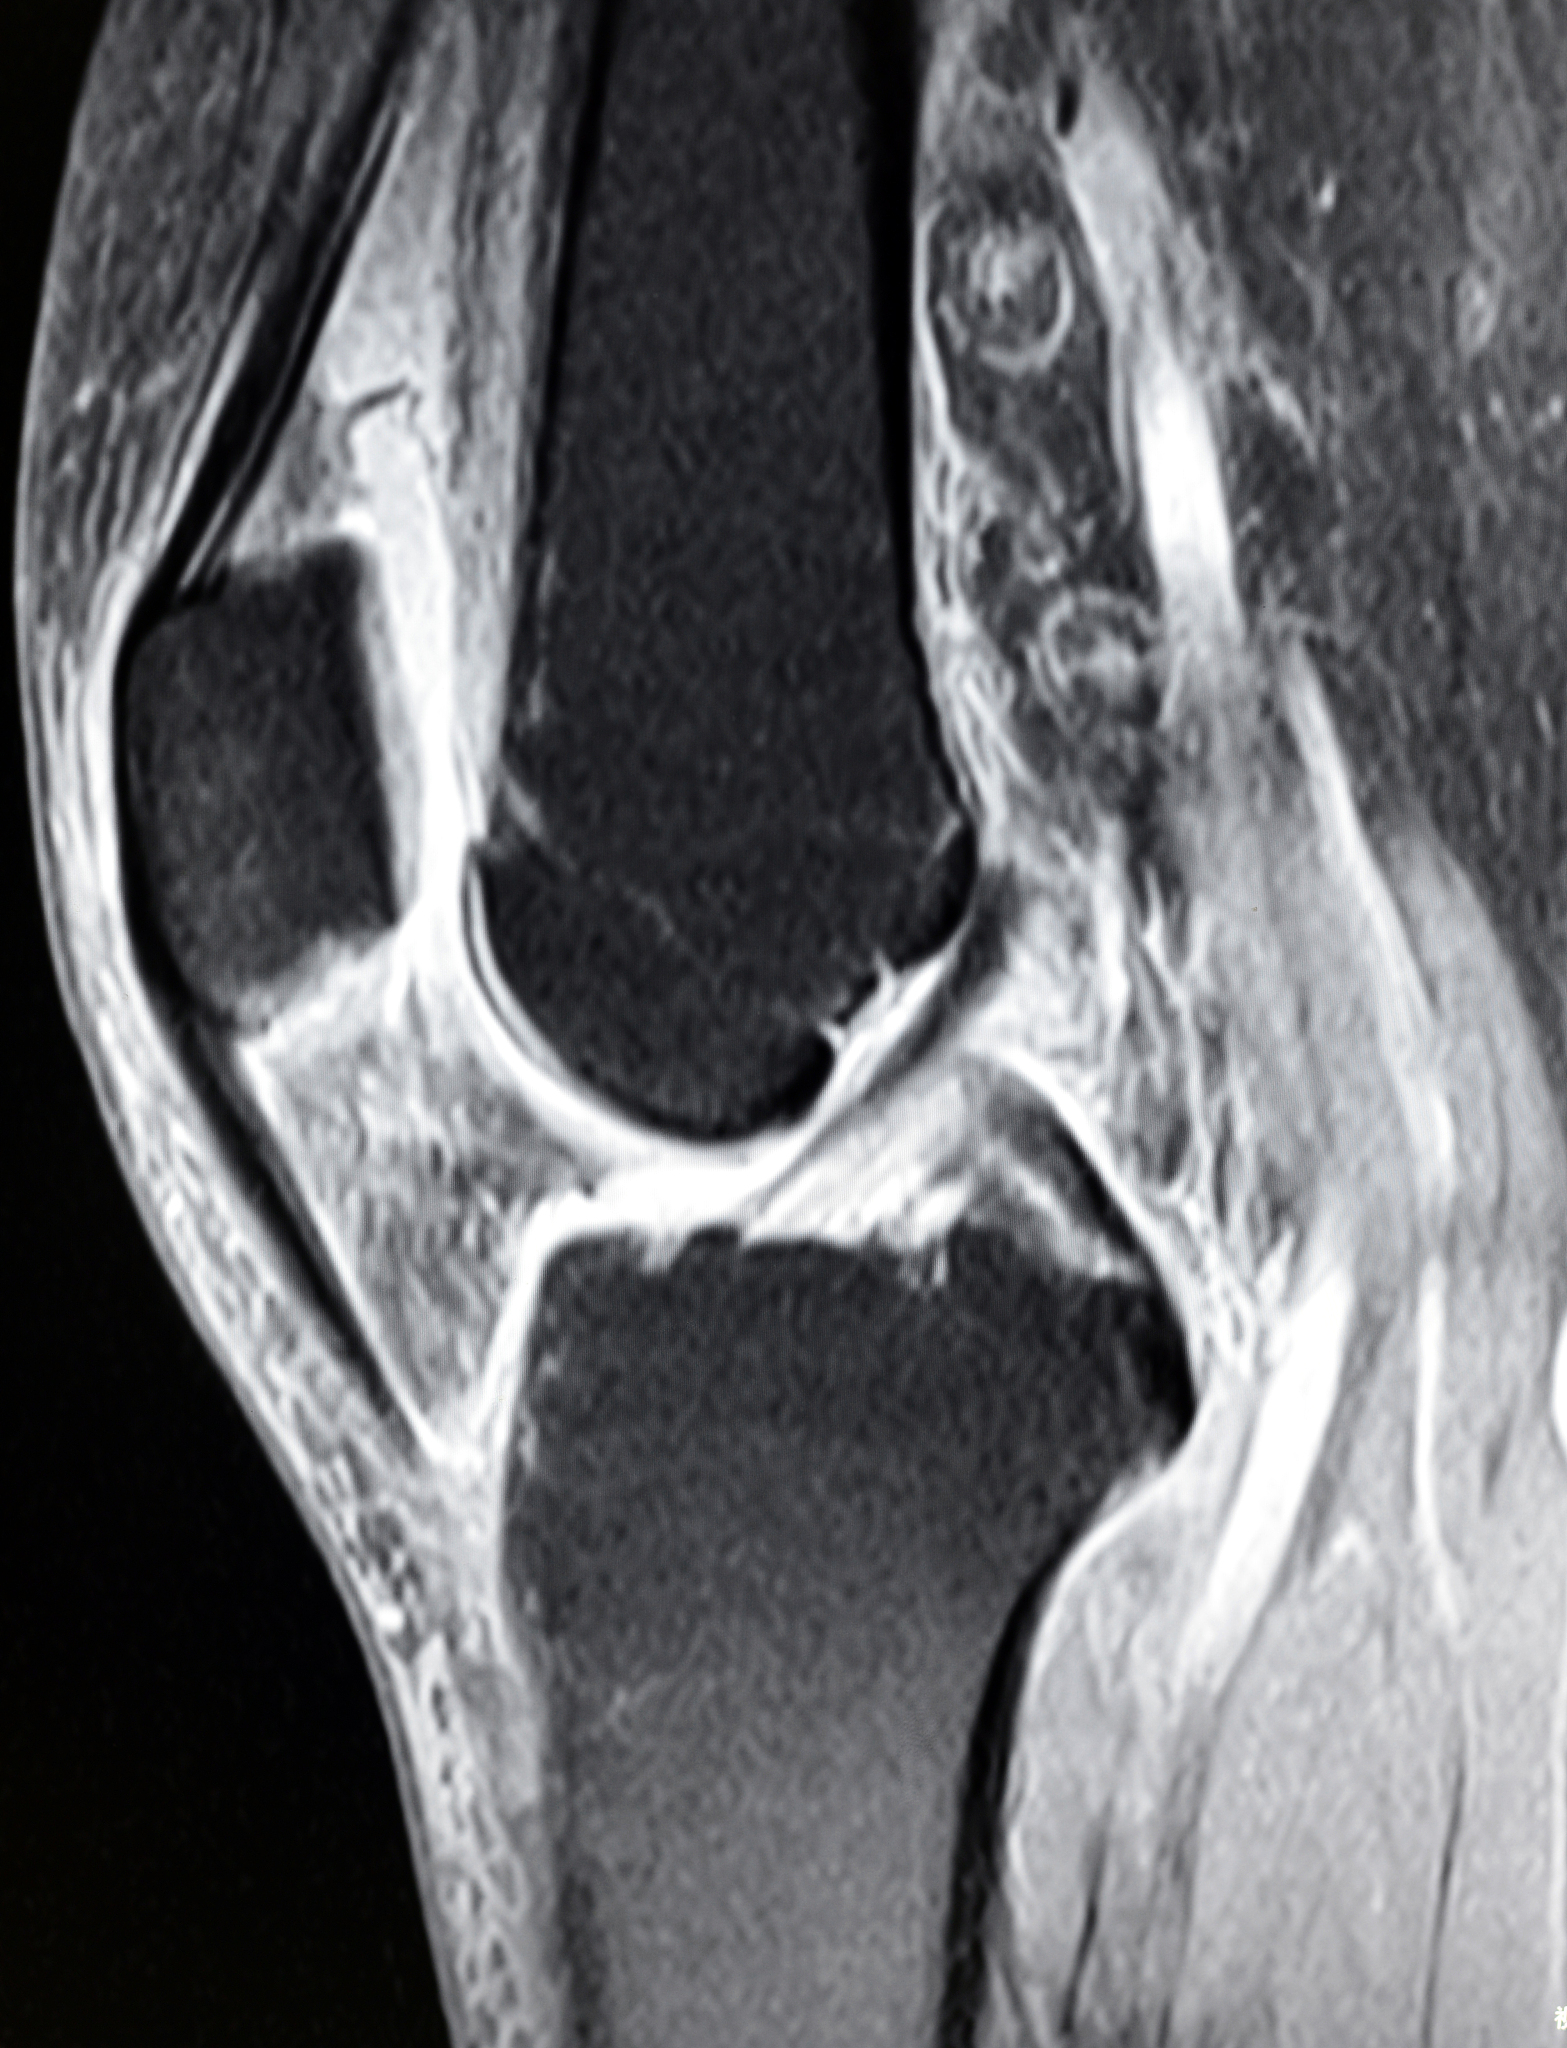

Ⅰ级:韧带肿胀减轻,韧带内高信号减弱或范围缩小,部分中断,关节腔有积液; Ⅱ级:韧带稍肿胀,韧带内高信号明显减弱或范围明显缩小,连续性存在,关节腔有少量积液; Ⅲ级:韧带无肿胀,韧带信号正常或轻度不均匀,关节腔无或少量积液。

Ⅰ级:韧带肿胀较前减轻韧带内高信号较前有所减弱或范围有所缩小连续性部分仍中断关节腔仍见积液;Ⅱ级韧带稍肿胀韧带内高信号较前明显减弱或范围明显缩小连续性存在关节腔少量积液。Ⅲ级韧带基本无肿胀韧带信号正常或仅有轻度不均匀关节腔内无或少量积液。精简描述